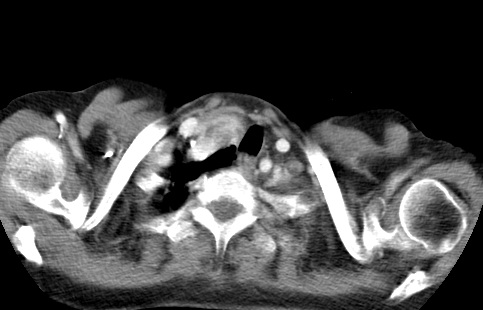

标题: CT23982:女67岁,胸部扫描时发现,甲状腺瘤? [打印本页]

标题: CT23982:女67岁,胸部扫描时发现,甲状腺瘤?

右侧甲状腺腺瘤!支持!不排除甲状腺癌可能!建议手术切除!

右侧甲状腺占位性病变,性质待定(甲状腺腺瘤?);建议:必要时行进一步检查。

右侧甲状腺占位性病变,性质待定(甲状腺腺瘤?);建议穿刺活检。

右侧甲状腺占位性病变,甲状腺腺瘤可能,建议穿刺活检。